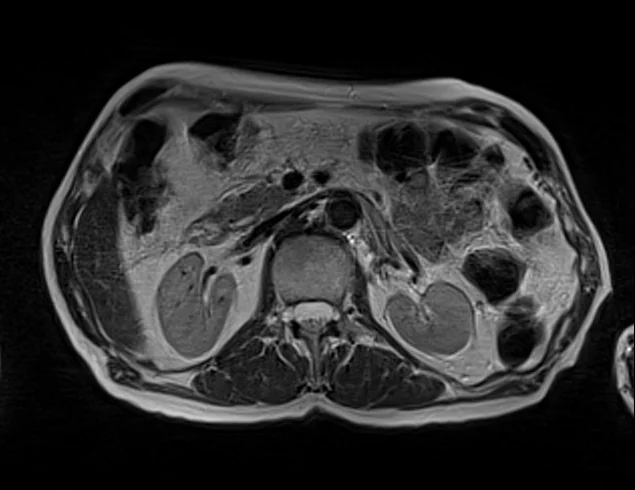

mrimaster

t2 1 - MRI